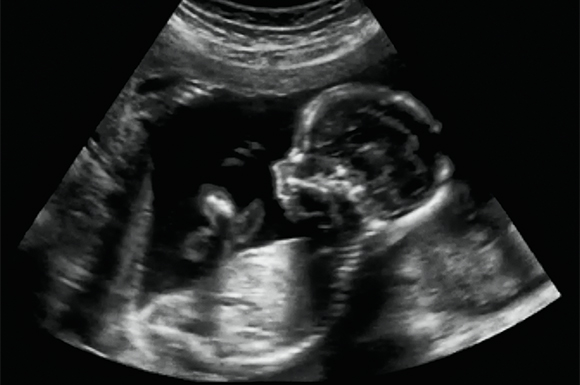

Este modelo de Comed capta los latidos cardíacos del feto gracias al efecto Doppler. El aparato esta compuesto de una parte de emisión-recepción de señales ultrasónicas, un tratador de señales y un parlante integrado para una presentación sonora de señales. Gracias a todos estos elementos la aparición del ritmo cardíaco fetal aparecerá en la pantalla de cristales líquidos y comandos.

El doppler fetal de Comed posee una pantalla de cristales líquidos permitiendo observar el resultado digital del ritmo cardíaco en tiempo real. La aparición del ritmo promedio se hará manualmente. Este producto esta equipado con una base de sonido, destinada a conectar los audífonos lo que nos permitirá además almacenar el audio captado.

El Doppler fetal y vascular Sonoline C, se basa en el audio que captará con la ayuda de una sonda compatible, los sonidos traducirán el ritmo cardíaco del feto y las transcribirán en sonidos a través del parlante que viene incorporado.

El Doppler fetal Sonoline C es muy ventajoso para las mujeres embarazadas que quieran guardar momentos únicos en la comodidad del hogar. De esta manera la futura mamá podrá sentirse mucho más cómoda para las ecografías en el seno de un hospital, ya que allí el material es mucho más técnico. Escuchar el corazón del bebe permite a las madres controlar la salud de su hijo, esta clase de práctica deberá ser aprobada por el ginecólogo o partera.

Gracias al ecógrafo portátil Sonoline B usted podrá escuchar los latidos del bebe con una ecografía a las 12 semanas de gestación. Este aparato revolucionario transmitirá los efectos de sonido con una claridad nunca antes lograda, este Doppler posee todas las características de un Doppler profesional.

Su uso es por consecuente totalmente inofensivo tanto como para el feto y la futura madre. Este ecógrafo portable para feto es enviado por un gel de ecografía. Lo que nos permitirá realizar una sesión ecográfica de alto nivel. El Sonoline B esta equipado con una pantalla LCD retro iluminada que nos indicará el ritmo cardíaco del feto.